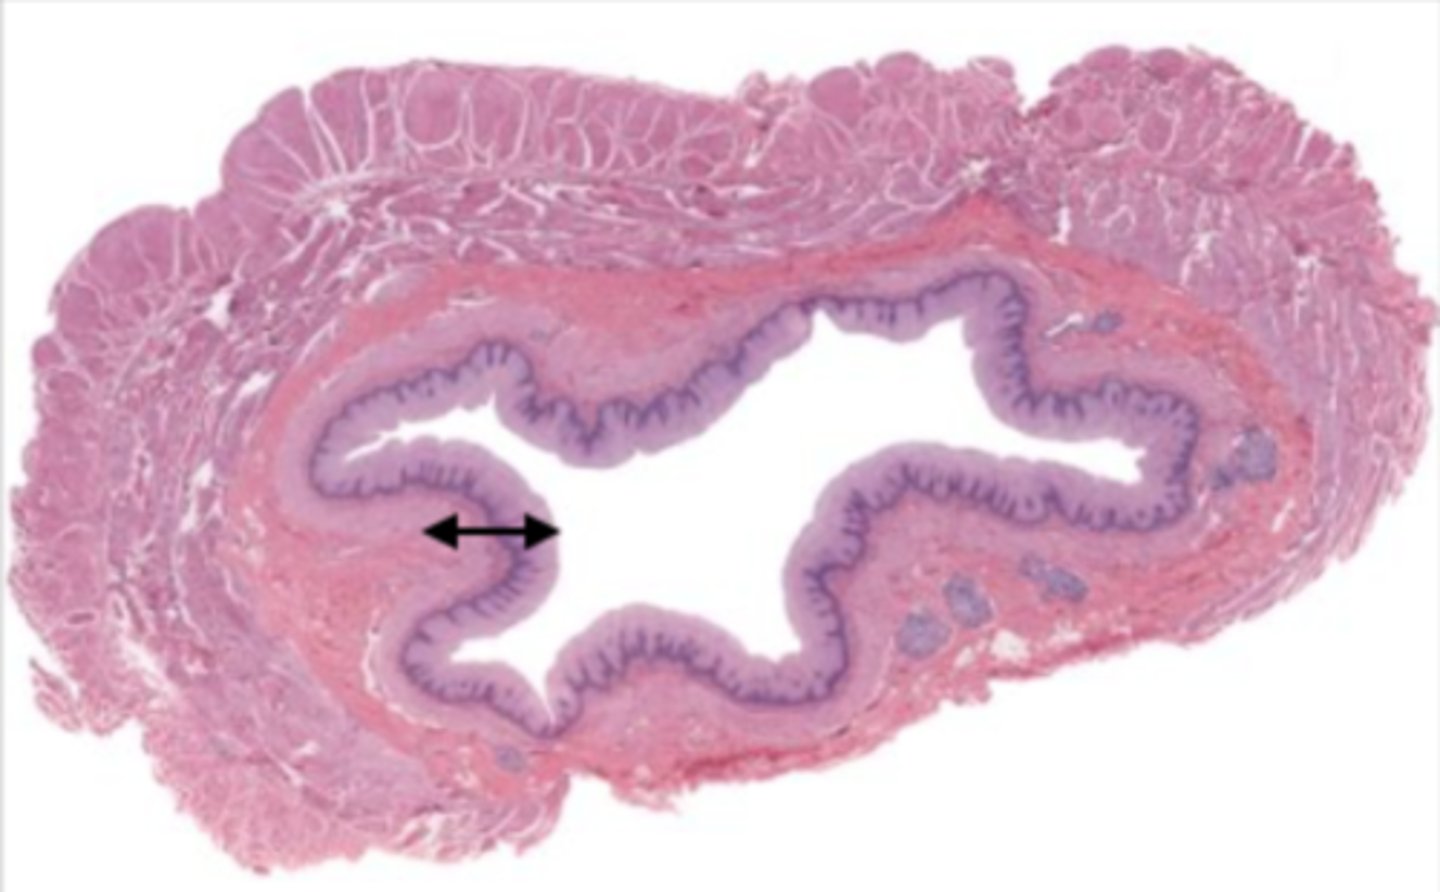

colon (histology)

simple columnar epithelium

what kind of epithelium lines the mucosa of the colon?

intestinal glands/crypts (colon)

lumen (colon)

mucosa (colon)

mucosal epithelium (colon)

lamina propria (colon)

muscularis mucosa (colon)

submucosa (colon)

contains glands and blood supply

muscularis externa (colon)

serosa/adventitia (colon)